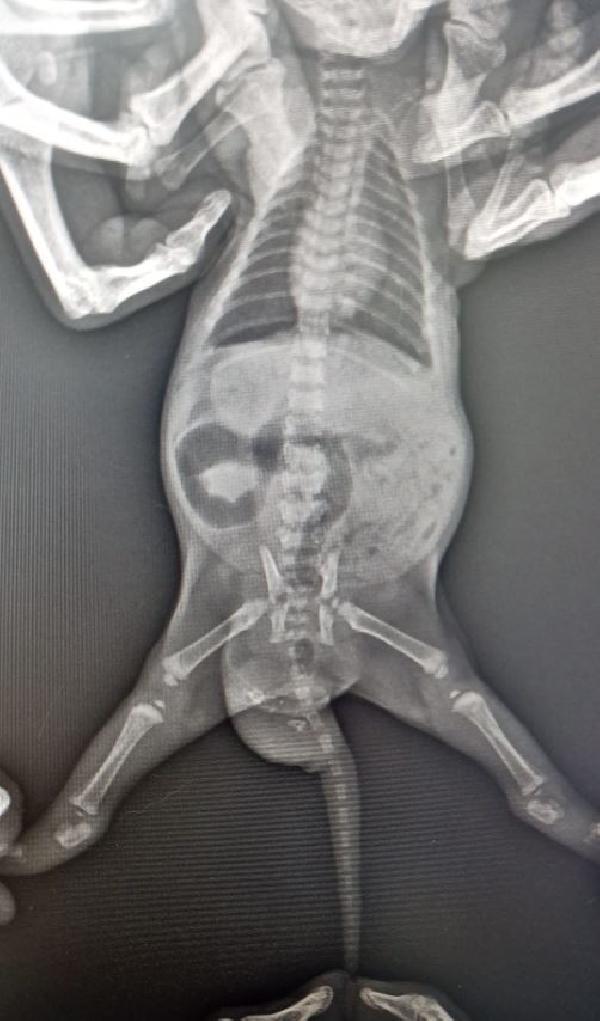

Büşra Nur Yıldız'ın siyam cinsi kedisi, yaklaşık 4 ay önce doğum yaptı. Doğan 2 yavru kediden birinin kuyruğunda şişlik olduğunu fark eden Yıldız, veterinere başvurdu. Veterinerde yapılan kontrolde kedinin kuyruğunda; dişleri, tüyleri, iskelet sistemi, kanal hücreleri oluşan yavru taşıdığı ortaya çıktı. Yavru kediye 'teratom' (canavar tümör) tanısı konuldu. Kedi cerrahi operasyona alınarak, tümör temizlendi. Şu an 4 aylık olan kedi, sağlığına kavuştu.

Ameliyatı gerçekleştiren veteriner hekimlerden Emir Düzgören, kedi ile ilgili vaka bildirim raporu hazırlayacaklarını belirterek, "Yavruyu anesteziye uygun hale geldiğinde röntgene aldık ve içeride kemik benzeri dokular olduğu tespit edildi. Ardından çocuğun kuyruğunun alt bölümüne teratom tanısı konuldu. Çoğalan hücrelerden birinin bir tümör hücresine dönüşmesi sonucu oluşmuş. Bu çocukta hem deri, kıl, kemik, kanal hücrelerinin tamamı gelişen canavar tümör oluşmuş. Kardeşi gibi düşünebiliriz; ama tıbbi olarak aslında bir tümör. Bilinen tek vaka bildirimi bizim dışımızda yurt dışında var. Vaka bildirim raporu hazırlayacağız, bunu bilimsel dergilere göndereceğiz. İkinci vakanın da gerçekleştiğini dünyadaki tüm veteriner camiası bilecek. Operasyon çok başarılı geçti. Diğer kardeşi ile aynı, operasyon izi dahi kalmadı. Çok heyecanlandık. Muhtemelen meslek hayatımızda bir daha böyle bir vakaya denk gelmeyeceğiz. Belki Türkiye’de bile bir daha böyle bir vaka olmayacak. Bize denk geldi" dedi.